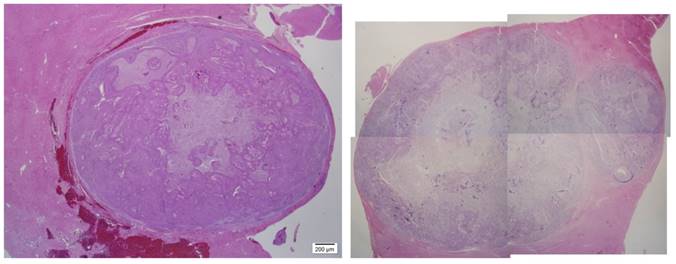

After the rabbits were sacrificed, gross pathology and histology was performed. Liver histology demonstrates a heterogeneous appearance to the tumor (Fig 4,5).

Figure 4

Histology. Hematoxylin & Eosin staining was performed confirming tumors within the liver on 10th day (H&E ×12.5)(A), and 44th day (H&E ×6.5)(B).